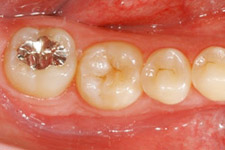

移植後4ヶ月。

移植歯はコンポジットレジンで修復が行われています。